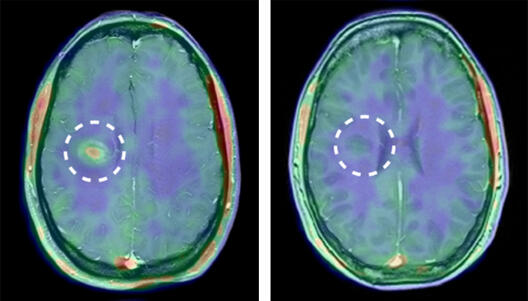

Inflammation in a human brain before therapy (left) and after therapy (right), combined positron emission tomography and magnetic resonance imaging (PET-MRI).

The results were impressive. The MMP tracer accumulated in the human brain even before any damage to the blood-brain barrier could be detected using the traditional method. “It really is something special to be able to corroborate something in a patient that had been discovered doing basic research in animal experiments,” says Dr. Sven Hermann, an expert in nuclear medicine and small animal imaging, “it’s what every scientist dreams of”. The scientists also observed, as they predicted, that little or no tracer accumulated after the patients had undergone anti-inflammatory therapy.